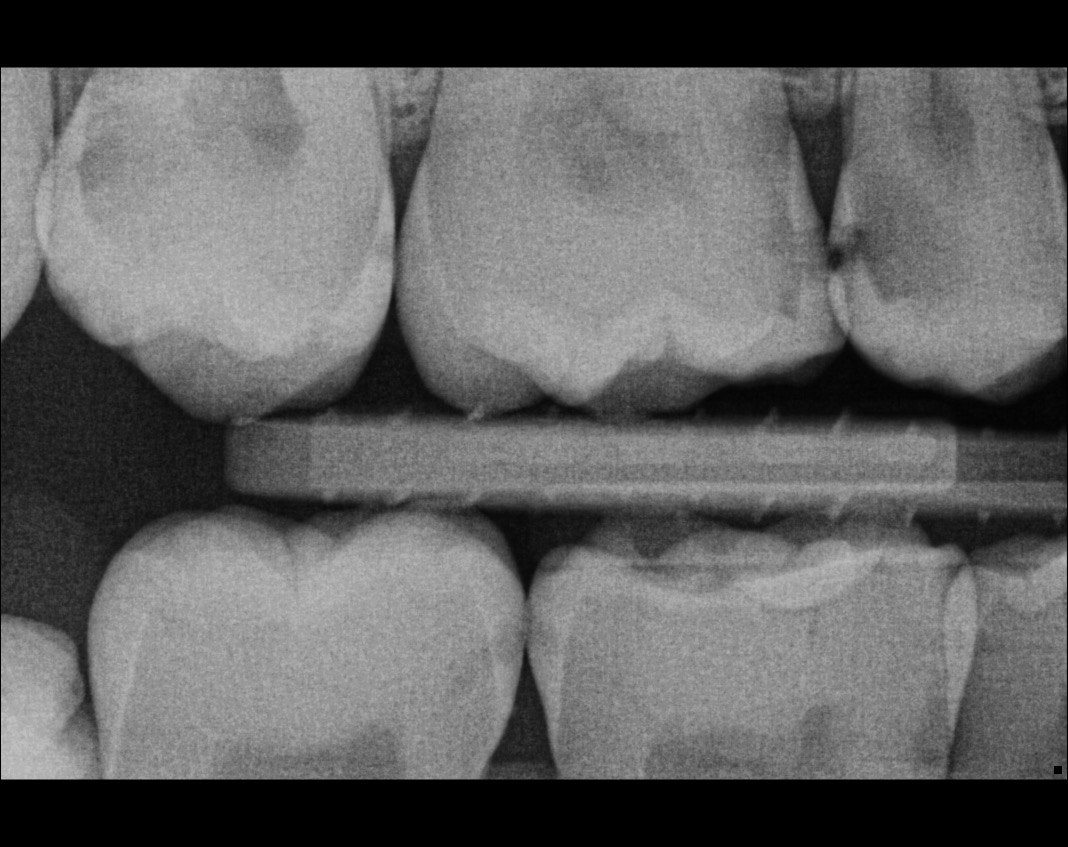

Question 14: What option can describe the mesial surface of the tooth # 3.4?

Question 15: What option can be selected for treatment of the caries in mesial surface of the tooth # 3.4?

Question 16: What option can be chosen for the treatment of the mesial surface of the tooth # 3.7?

Question 17: What are the caries extention in distal of the tooth # 2.4 and mesial surface of the tooth # 2.5 respectively?

Question 18: What is the option that can describe the distal surface of the tooth # 1.7?

Question 19: What is the option that can describe the mesial surface of the tooth # 1.8?

Question 20: What is the option that can describe the distal surface of the tooth # 4.5?

Question 21: What options can describe the mesial and distal surfaces of the tooth # 4.7 respectively?

Question 22: What codition cannot be seen in the lower teeth in this X ray?

Question 23: What option can describe the distal surface of the tooth # 4.5?

Question 24: Which condition can be detected in the following X ray?

Question 25: What treatment is appropriate for distal surface of the tooth # 3.4 and mesial surface of the tooth # 3.5?